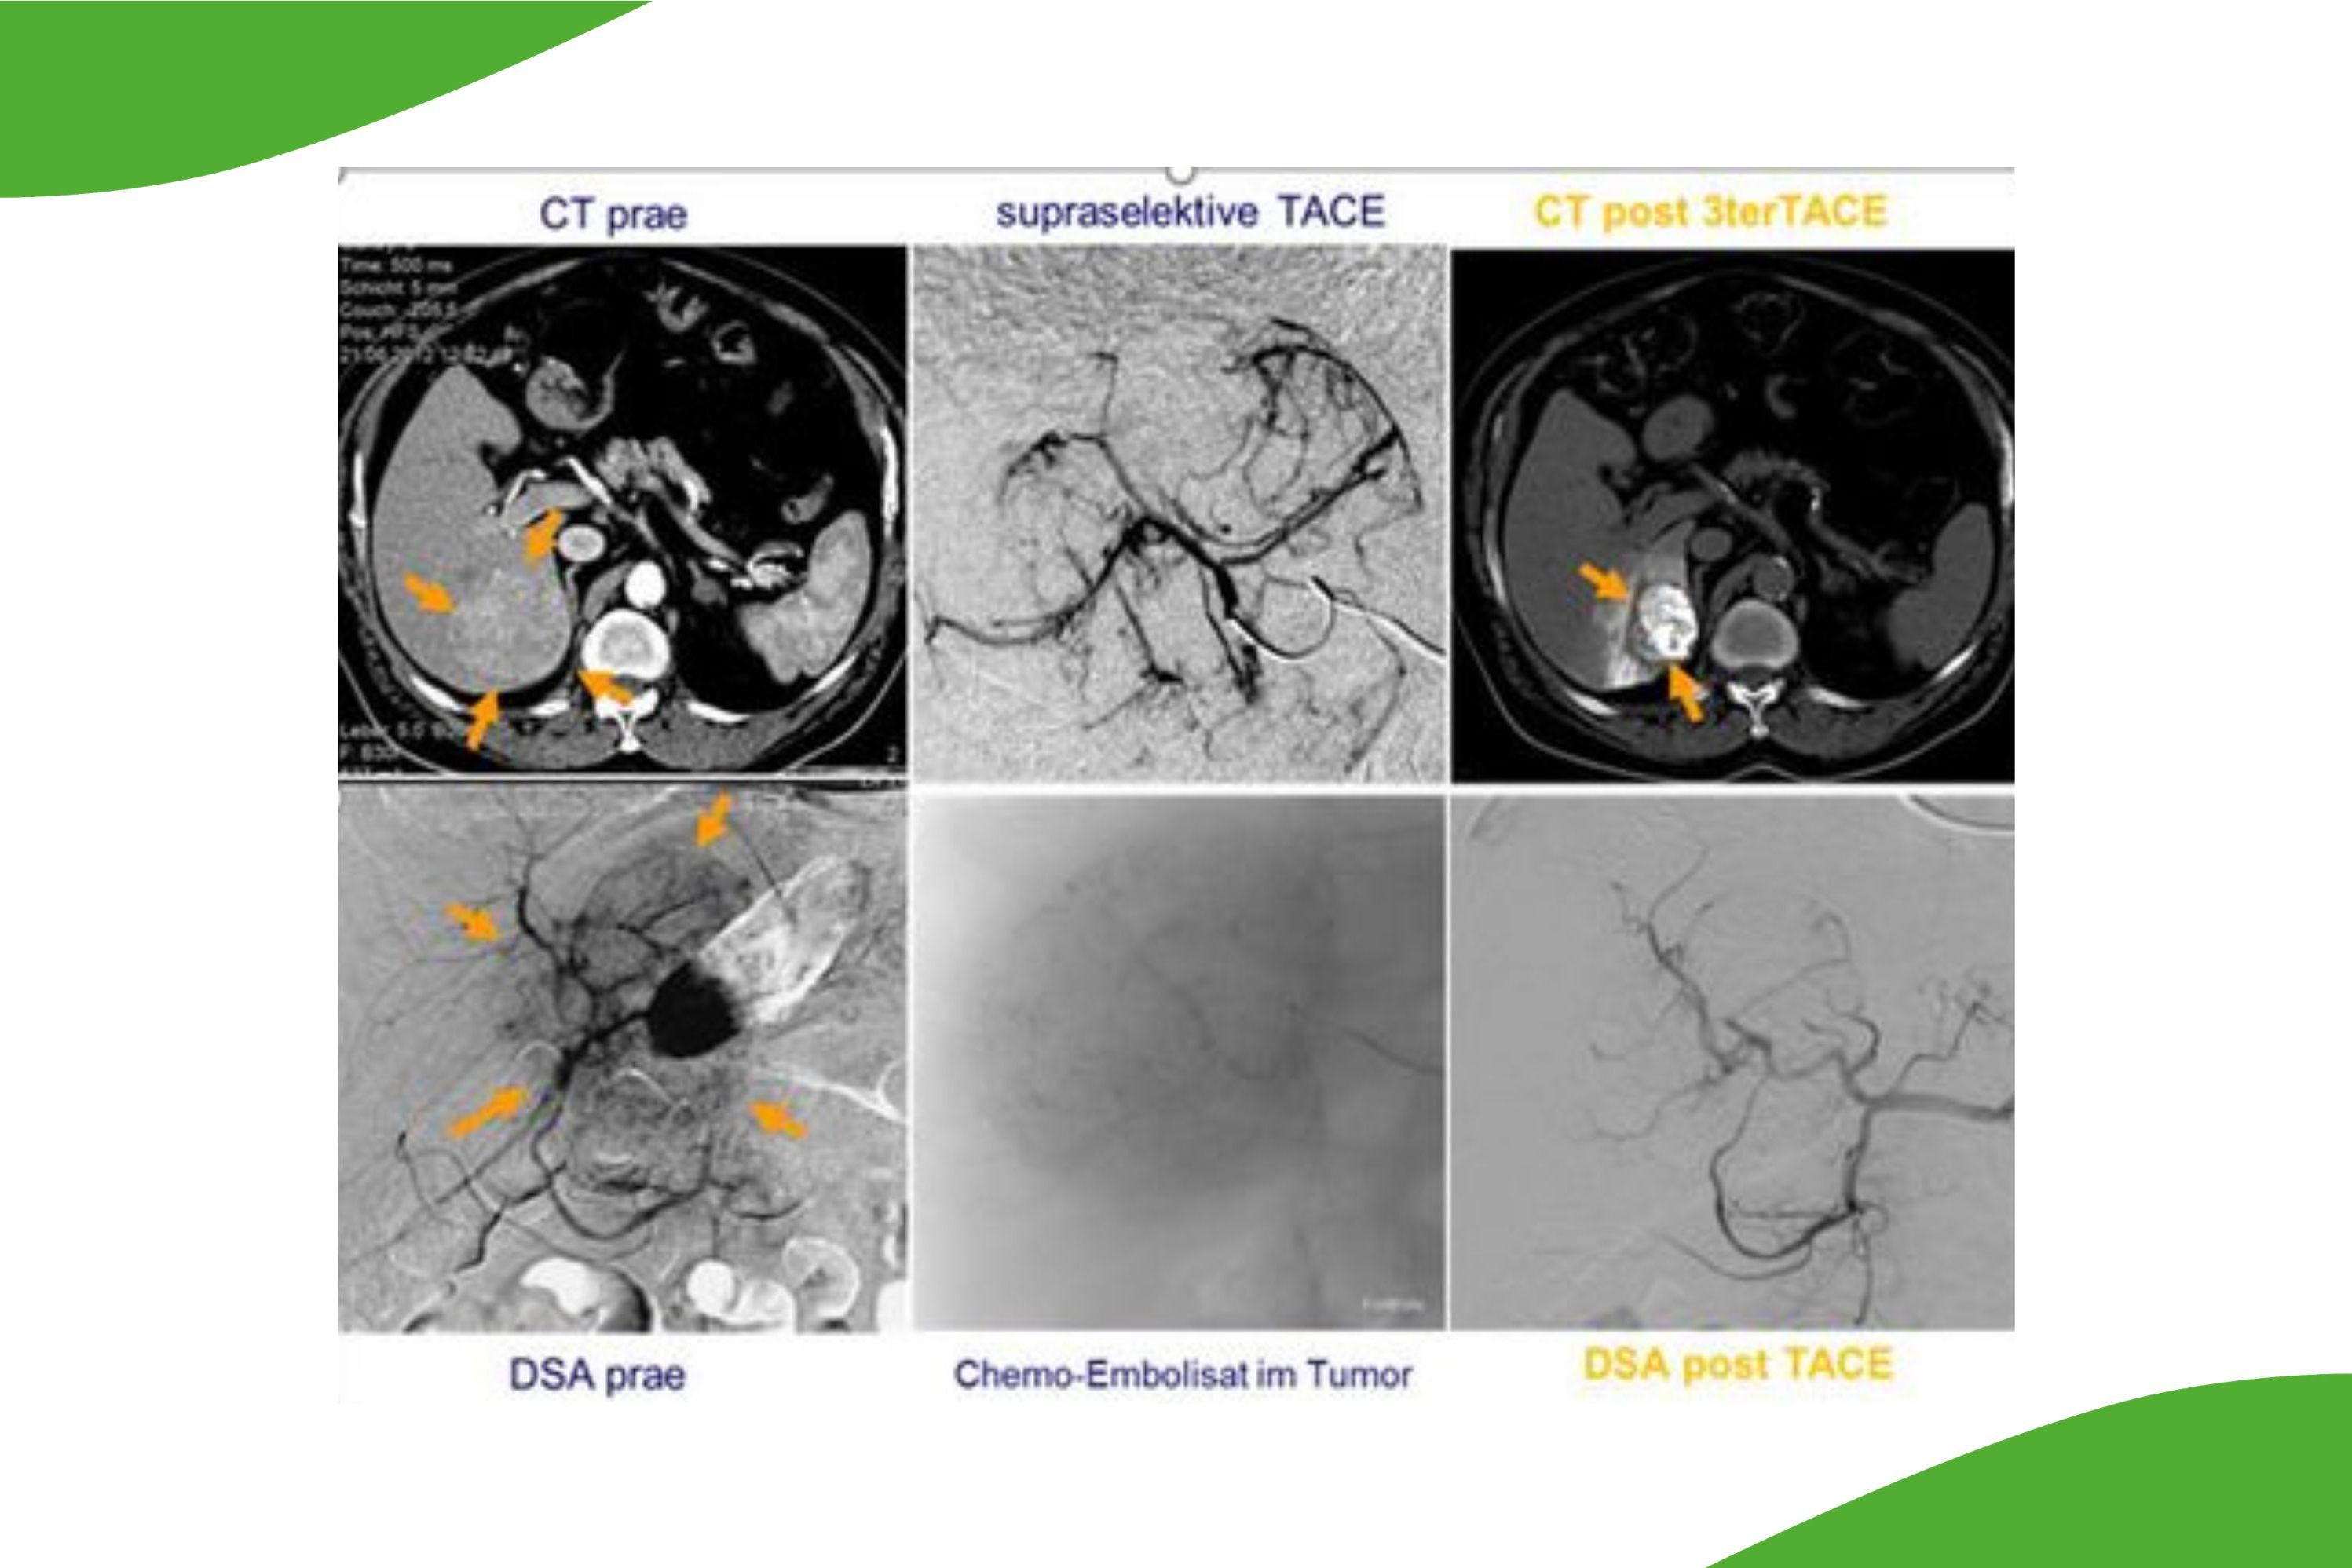

05. Transarterielle Chemoembolisation von Lebertumoren (TACE). Hier wird das Chemotherapeutikum über einen dünnen Katheter direkt in den Tumor gegeben und die Tumorgefäße anschließend verschlossen. Hierdurch lässt sich die Menge des Chemotherapeutikums deutlich reduzieren mit konsekutiv geringerer Nebenwirkungsrate, bei gleichzeitig deutlich stärkerer Wirkung im Tumor. Bei Gabe über eine Armvene sind wesentlich größere Mengen erforderlich.

Mit speziellen Mikrokathetern können selektiv die blutversorgenden Gefäße zu einem Tumor aufgesucht werden und diese können dann entweder mit kleinen Partikeln oder Embolisaten verschlossen werden, so dass die Tumore von der Blutversorgung abgeschnitten sind. Hierdurch kann es zu einer Schrumpfung der Tumore kommen. Verschiedene Tumore können gleichzeitig auch mit einer lokalen Chemotherapie behandelt werden, so dass die systemische Wirkung reduziert ist, aber der Tumor lokal verstärkt behandelt wird. Diese Verfahren können gut mit der Embolisation, also dem Gefäßverschluss, kombiniert werden. Beispiel einer solchen Behandlung wäre die transarterielle Chemoembolisation (TACE) beim Lebercarcinom (HCC) (Abbildung), aber auch bei verschiedenen Metastasen kommen solche Verfahren zum Einsatz. Neu etabliert haben sich hier spezielle kleine Partikel, welche mit speziellen Chemotherapeutika beladen werden können, so dass diese sich im Kapillarbett der Tumore verankern und hier lokal verlängert die Wirkung entfalten können. Beispiele wären die sogenannte DEBIRI-Behandlung. In einigen Fällen kann eine kathetergesteuerte Tumortherapie auch mit einer perkutanen Thermoablation (z.B. die CT-gesteuerte Mikrowellenablation) kombiniert werden, um den Therapieeffekt zu verbessern. Welche kathetergesteuerte Tumortherapie in Frage kommt, wird im interdisziplinären Tumorboard bzw. im Onkovaskulären Zentrum des Klinikums Saarbrücken besprochen.

Als weitere neue Möglichkeit kann nun auf der neuen Angiographieanlage im Klinikum Saarbrücken die kathetergesteuerte Tumorchemoembolisation mit einer perkutanen Direktpunktion zur Thermoablation kombiniert werden, und das in einer Sitzung auf einem Gerät. Hierzu werden MRT- oder CT- Datensätze in Echtzeit mit der DSA-Angiographie und mit einer Flachdetektor- CT (sogenanntes Dyna-CT, erstellt auf der Angiographieanlage) dreidimensional fusioniert.

Nicht barrierefrei: Die grafische Darstellung zeigt in sechs Bildern den Verlauf einer transarteriellen Chemoembolisation (TACE) bei einem Leberkarzinom (HCC).